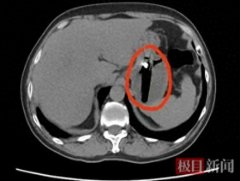

• 男子胃部隐痛反复一月竟是醉酒后误吞打火机

打火机 陈先生 反酸 2026/01/22